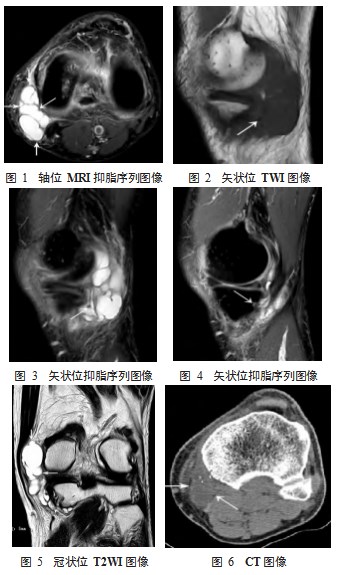

2.1 影像学表现特征 MRI 均扫描单膝关节(图 1~5 ), 其中病灶位于左膝 10 例,右膝 5 例。2 例行膝关节 CT 检 查者扫描双膝,也为单膝患病(图 6)。病灶较小者多位 于胫骨近端前内 2~3 cm ,半腱肌、股薄肌和缝匠肌的肌 腱的联合腱止点与内侧副韧带之间,较大者上达股骨内侧髁后内上方,股内侧肌内侧及缝匠肌、半腱肌、半膜肌间 联合肌腱间。病灶在 MRI 上边缘清楚,可见囊壁,囊壁 外缘欠规则,与周围软组织间及内部多可见薄层低信号分 隔。病灶多呈典型的囊性信号:长 T1WI、长 T2WI、抑 脂序列呈较均匀高信号,病灶多呈分叶状、多房样。病灶 大小: 3.3 cm×1.7 cm×1.9 cm~7.6 cm×4.1 cm×.3.7 cm。2 例 可见病灶向胫骨骨髓内延伸,骨皮质可呈类似于肿瘤扇贝 形外观(图 4)。

2.2 病灶内钙化的显示 2 例行双膝关节 CT 扫描,病灶 在 CT 上显示远不如 MRI 直观明确, 但调节适当的窗宽 窗位,仍可见略低于肌肉密度的病灶、隐约可见病灶内 的分隔,其中 1 例可见病灶内散在点状钙化(图 6), 而 MRI 对点状钙化的显示较差。

图 1~6. 68 岁同一男性鹅足滑囊炎患者的膝关节 MRI 及 CT 图像,可见膝关节内侧部呈分叶状排列的病灶(箭 头) ,并向胫骨骨髓内延伸(图 4 箭头) ,伴周围软组织 受压移位。